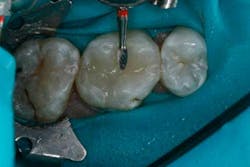

The depth of the cavity was determined to be 4 mm or less. The bulk-filled composite (Tetric EvoCeram® Bulk Fill) was placed in the preparation (Figs. 9 and 10). In this case, the first increment was placed, followed by additional material that was adapted to the tooth anatomy (Figs. 11 through 13). After further refining, the bulk-fill composite was light-cured in one increment for 10 seconds (1,200 mW/cm2).